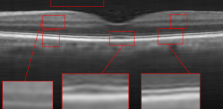

The proposed algorithm has been also tested for the super-resolution of the two other datasets. For dataset2, the middle slices of several 3D image have been selected for test and averaged with 2 previous and 2 next slices. The weights ’s set equal to for each B-scan. For the proposed approach, the patch sizes were set equal to 5 and 7 or (5 and 10) with window size equal to [2,2]. For MDT the window size was set to [2,2]. The results for the super-resolution of artificially missed B-scans of dataset2 with missing ratio have been illustrated in Fig. 6. Since this dataset does not contain reference images, PSNR and SSIM could not be reported. Hence, only visual comparison and the resulting CNR’s, with the following definition, have been reported for each algorithm:

where and are the mean and standard deviation of the foreground respectively and and are the mean and standard deviation of the background region, respectively. Averaged CNR’s for 5 Regions Of Interest (ROI) in each image (relative to an ROI selected in the background region of the image) have been computed. Note that ROI’s have been shown with red boxes in each image of Fig. 6. As the results show, the proposed algorithm results in a better output and higher CNR comparing to the other algorithms.